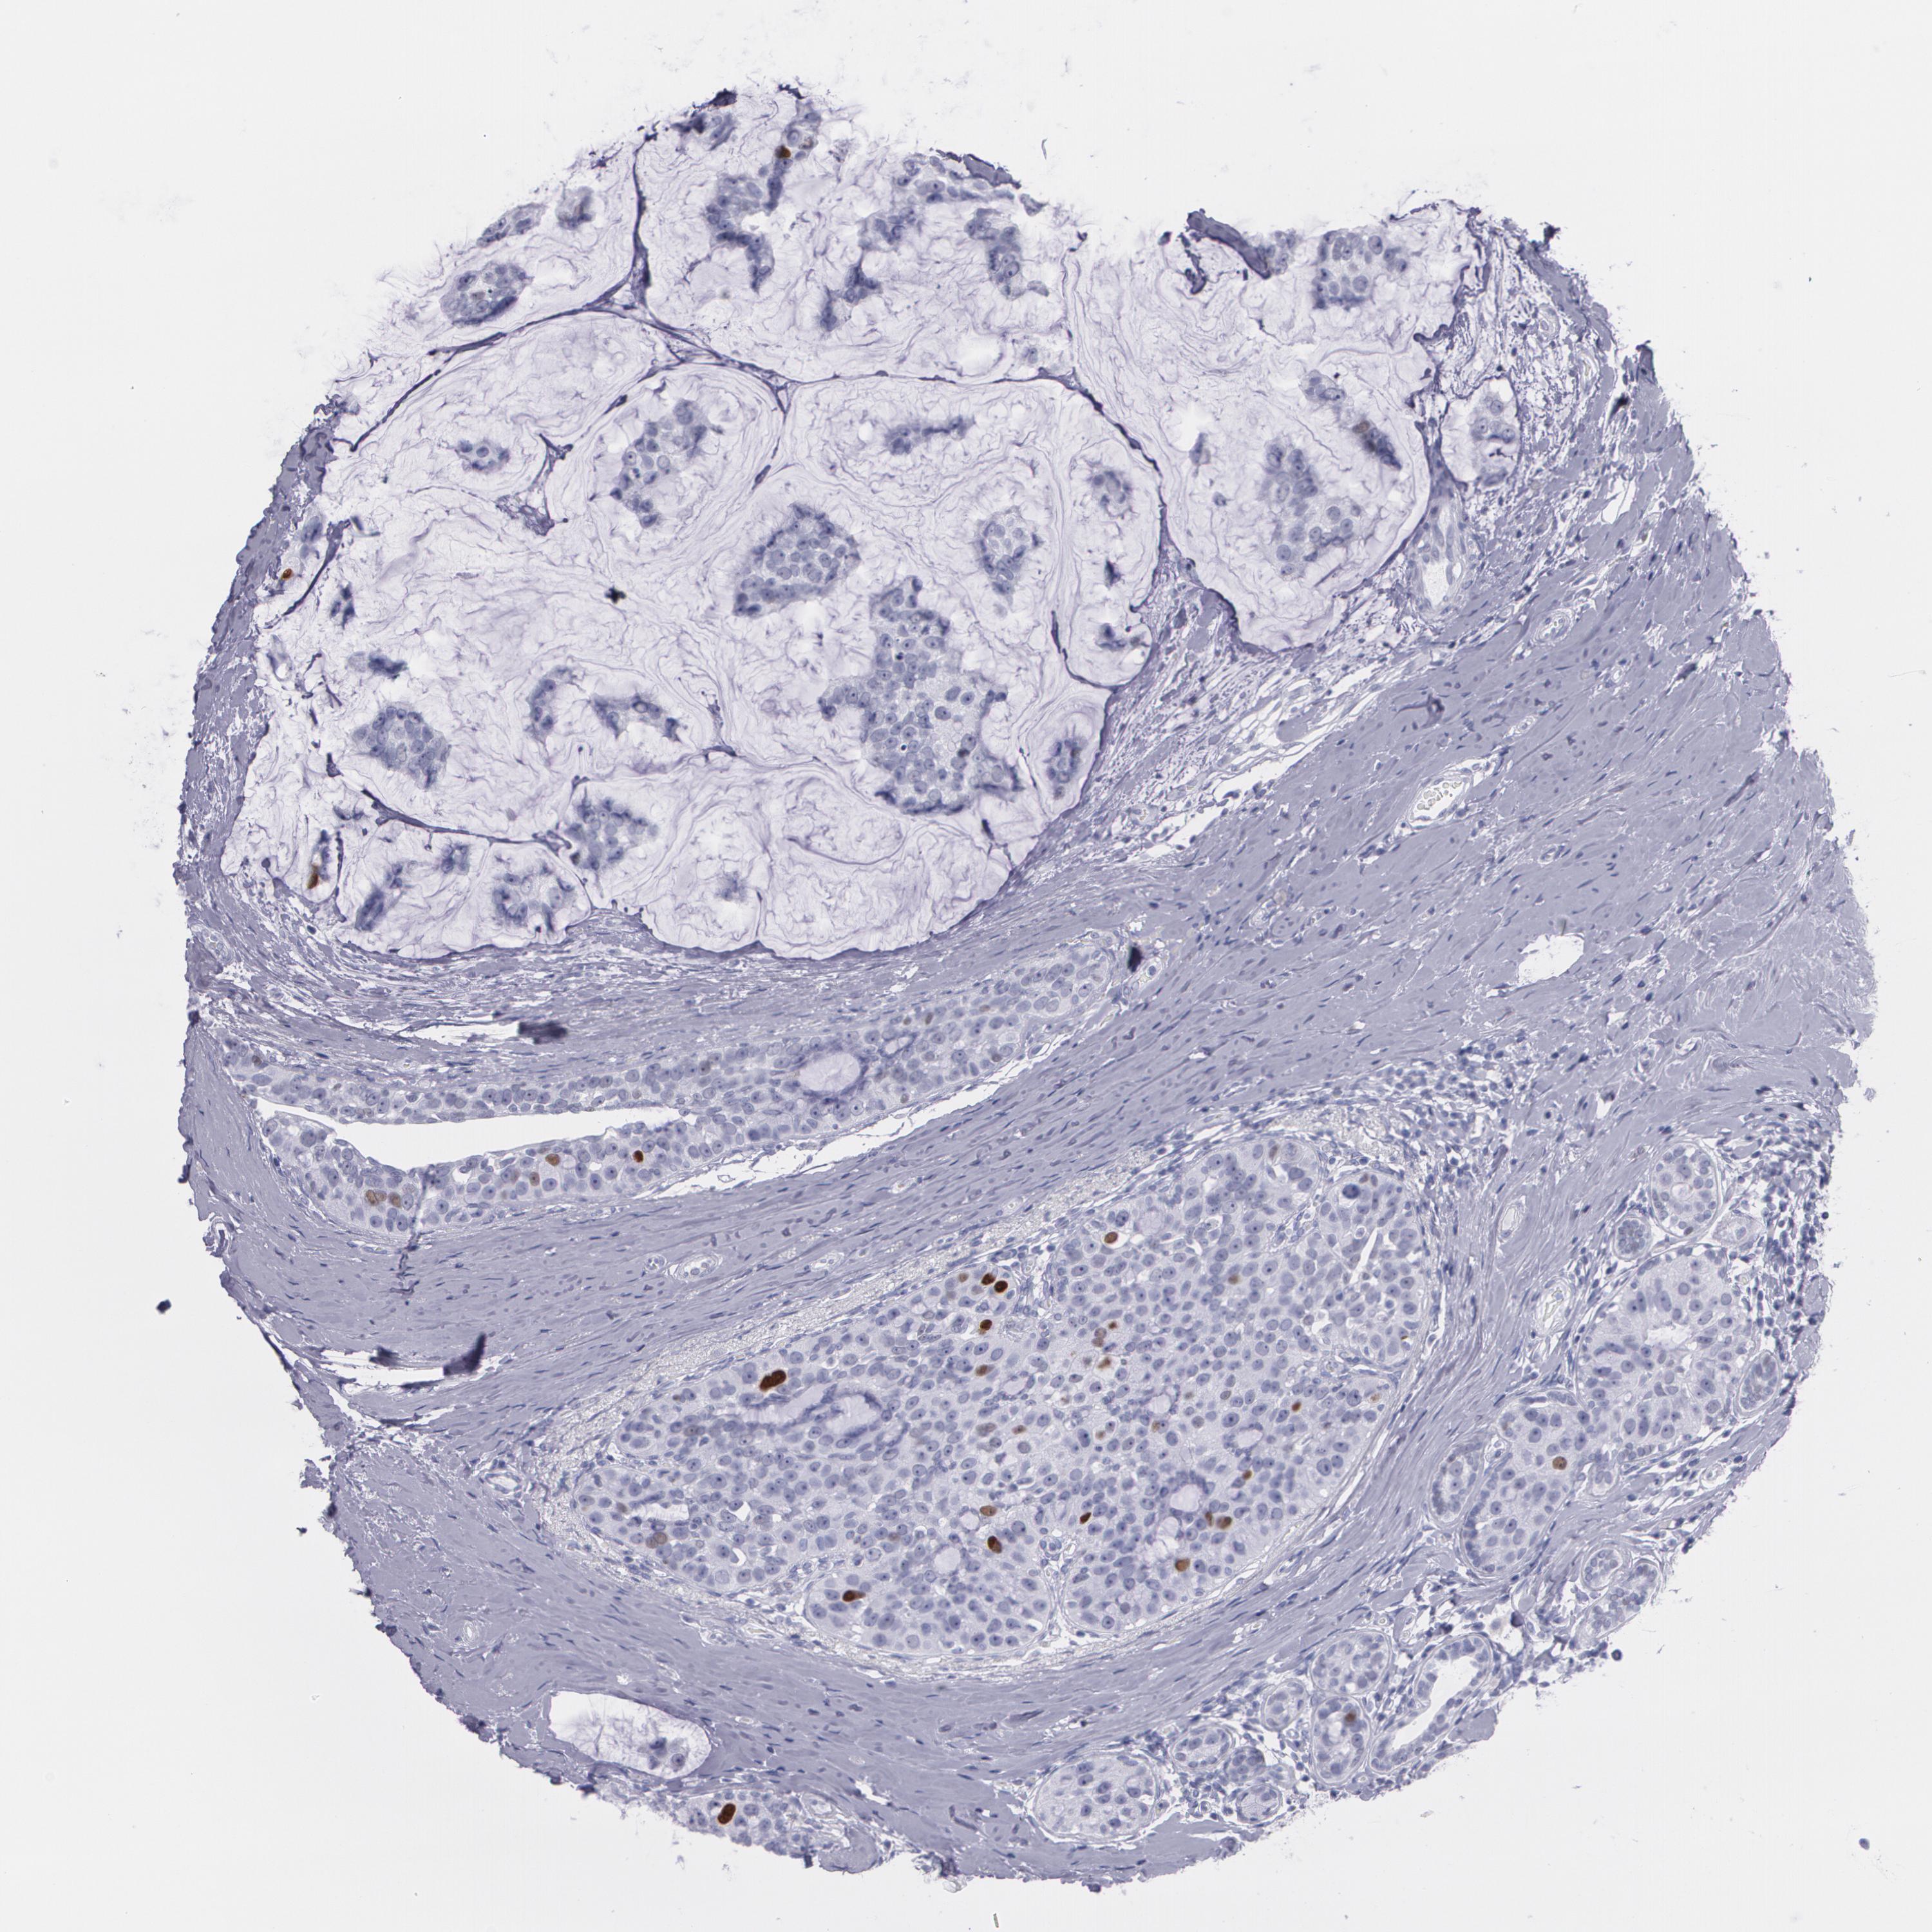

BRCA TCGA BRCA VALIDATION PROTEIN EXPRESSION

ANTIBODIES

AND

VALIDATION